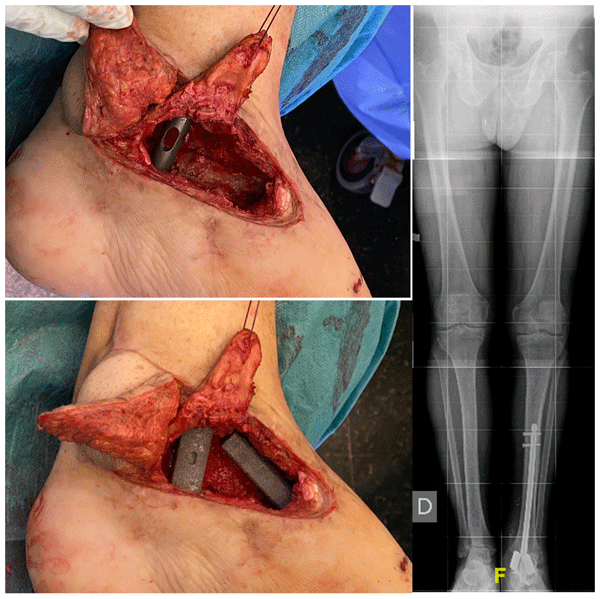

Complete talectomy for post-traumatic osteomyelitis (and/or avascular necrosis): report of a new technique

Daniel Pérez-Prieto, Alois Baumer, Jan Martinez-Lozano, Julian Aquilina, Paul Zamora, Albert Alier, and Lluïsa Sorlí

J. Bone Joint Infect., 10, 419–424, https://doi.org/10.5194/jbji-10-419-2025,https://doi.org/10.5194/jbji-10-419-2025, 2025

Short summary